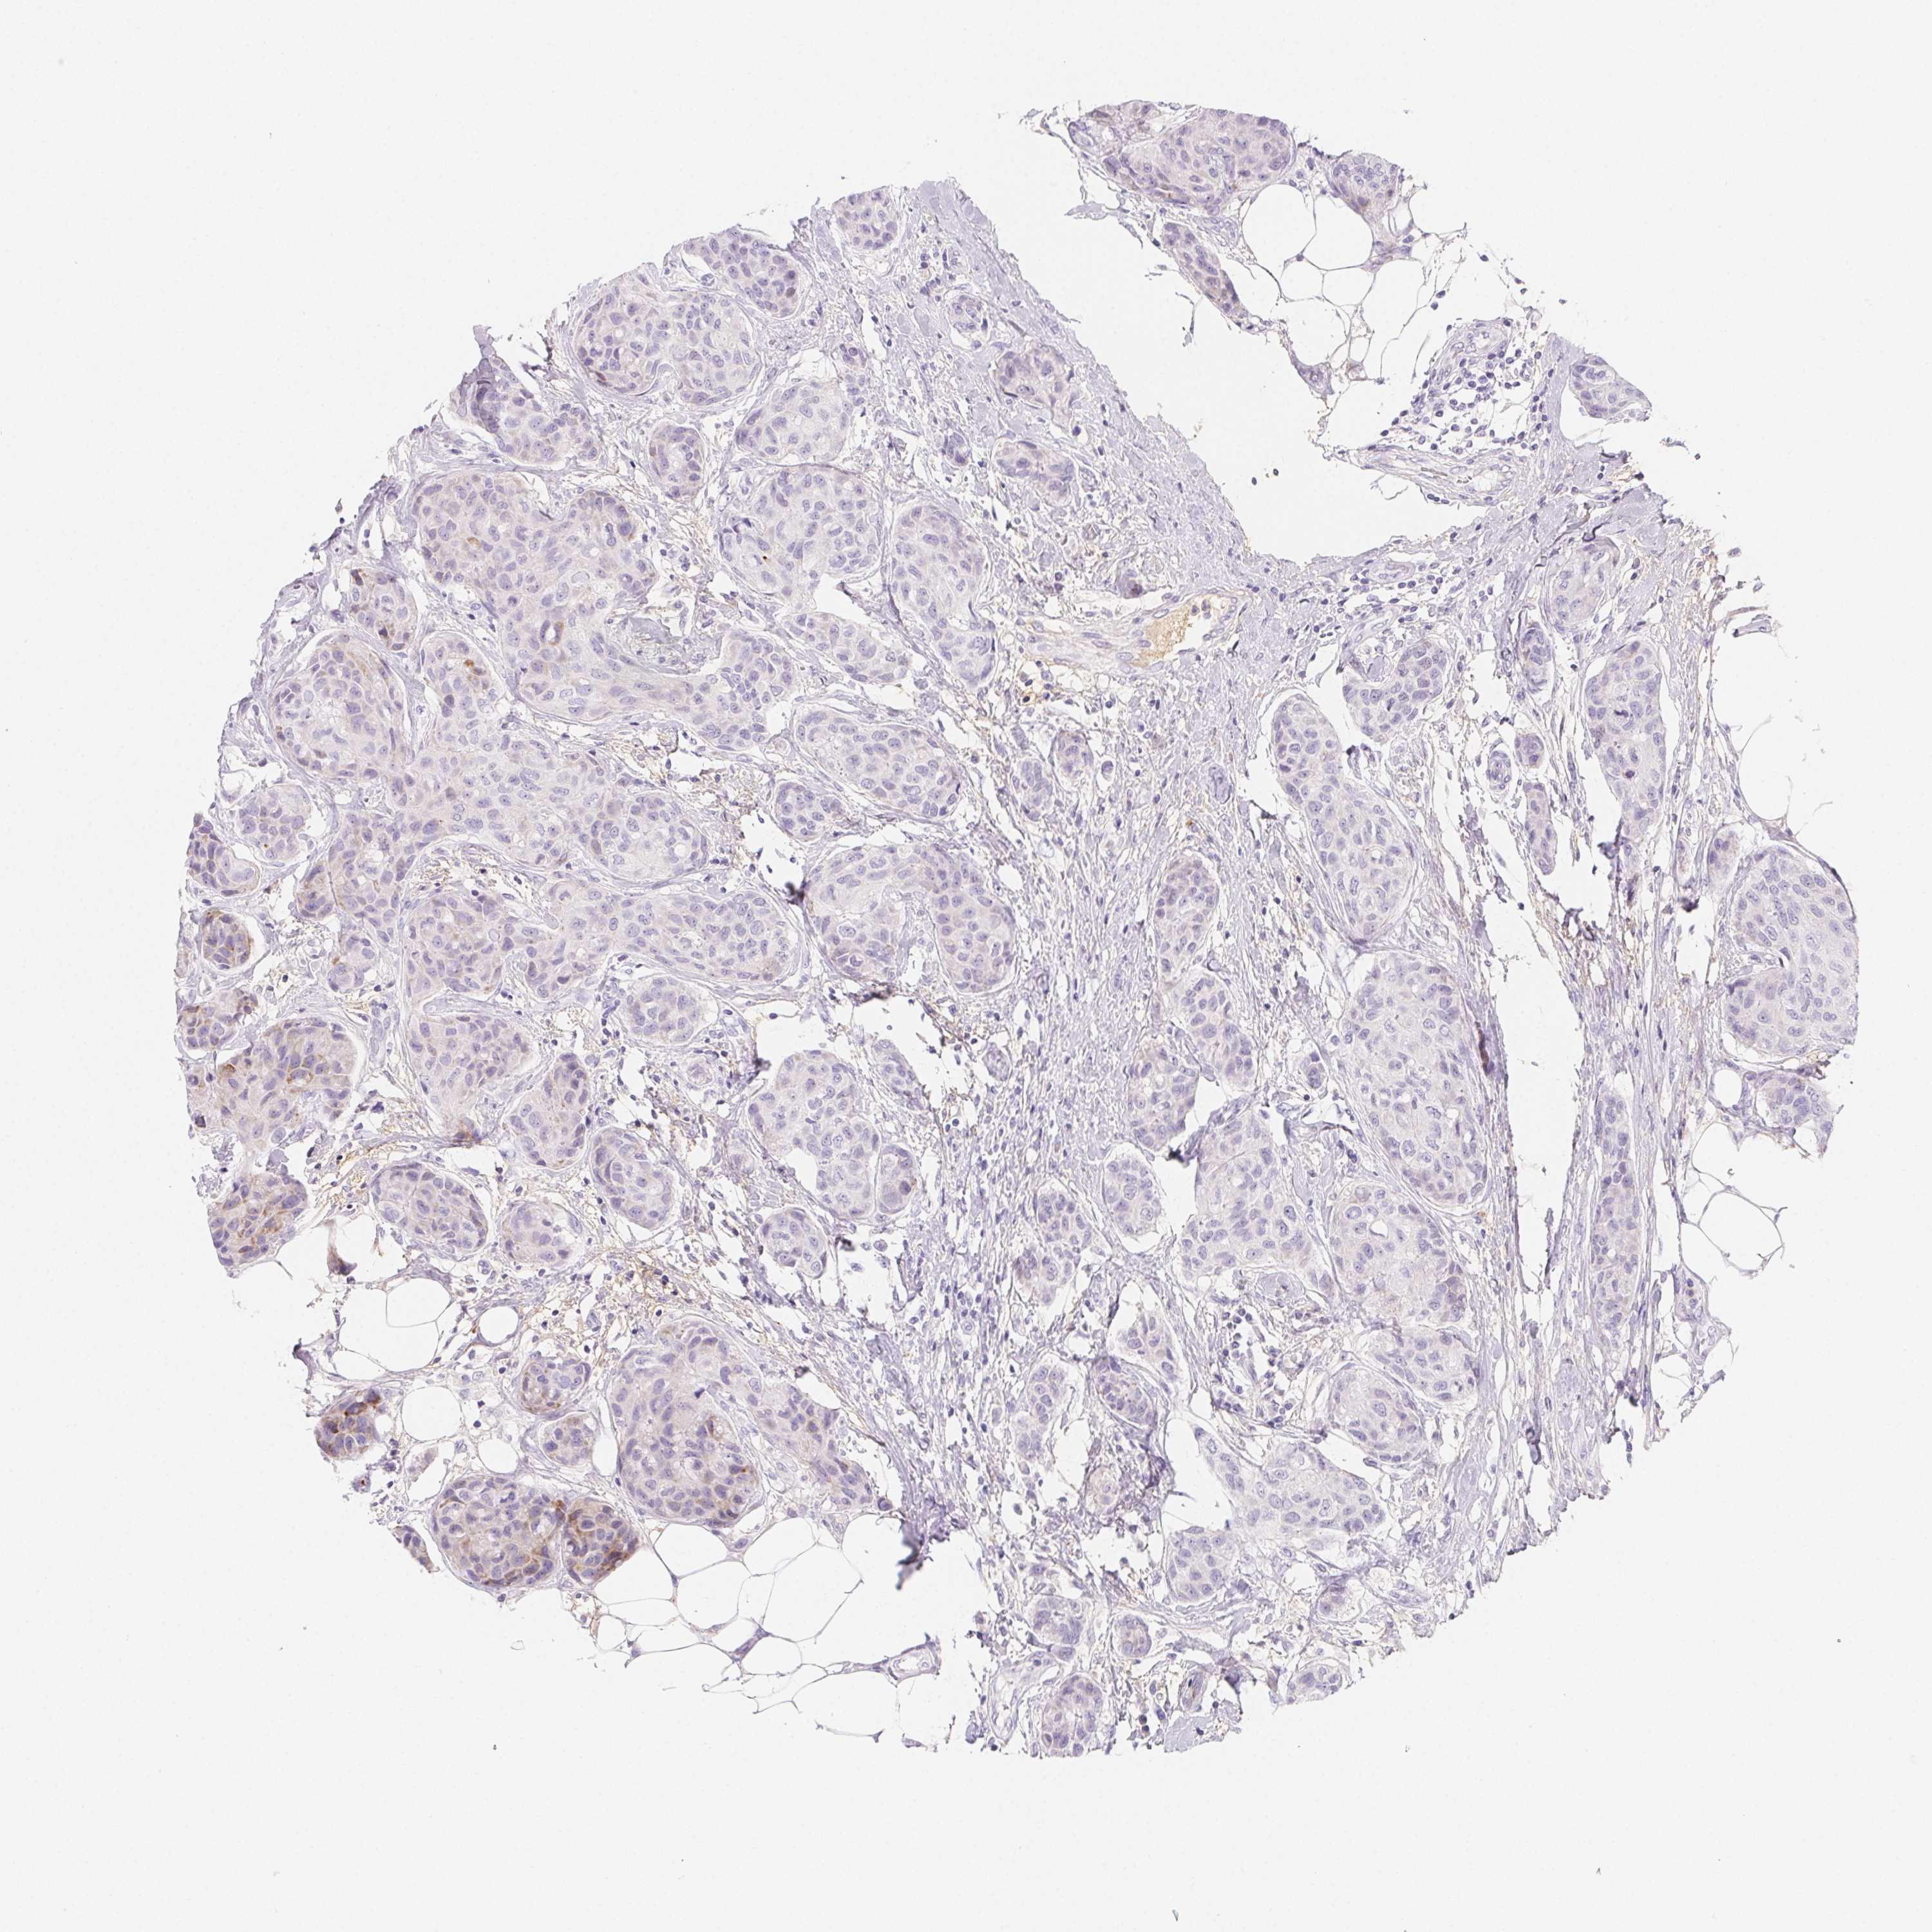

BRCA TCGA BRCA VALIDATION PROTEIN EXPRESSION

ANTIBODIES

AND

VALIDATION